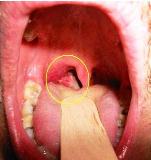

Рак горла трудно диагностировать из-за того, что его ранние проявления легко спутать с обычной простудой. Самыми первыми признаками являются регулярные гортанные боли, затруднение глотания, опухоли в области шеи, изменение голоса. Обнаружив перечисленные признаки, стоит сразу обращаться к врачу, не ожидаясь проявления явных симптомов рака горла. Ранние стадии рака могут сопровождаться появлением в горле небольших язв или белых пятен, но подобные симптомы наблюдаются лишь в 20% случаев.

Даже на основании явных симптомов диагностировать рак горла нельзя, поэтому врачом назначаются дополнительные исследования. Точно определить наличие раковых клеток поможет биопсия, а компьютерная томография позволит получить точное изображение опухоли.